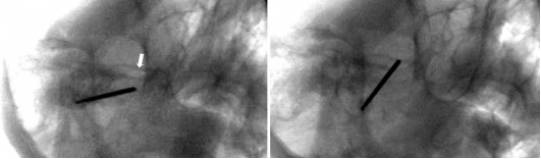

穿刺骨孔首先需要完善术前颅底CT扫描,骨化的翼棘或翼突韧带或其它骨孔内骨脊会妨碍穿刺成功。因此,作者推荐使用术中导航定向准确地引导放置穿刺针。

图14. 注意图中黑色箭头尖端所指的右侧卵圆孔内侧存在一骨脊(左图);该骨脊会使穿刺针难以通过骨孔;术中CT导航下放置穿刺针(右图)。